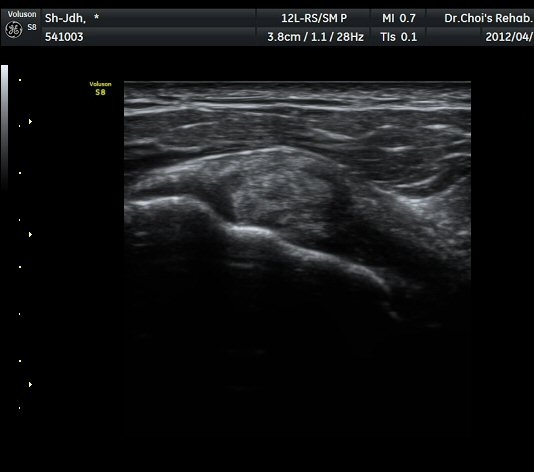

À̵ιڱ٠Ⱦ´Ü¸é°Ë»ç¿¡¼­ À̵ιڱٰÇÀÇ ºñÈĸ¦ º¸ÀÓ(»çÁø 1, 2).

À̵ιڱٰú ÀÌ¿ôÇÑ °ß°©ÇÏ±Ù°Ç »óºÎ¿¡¼­ ±¹¼ÒÀûÀÎ ¿¬°á¼º ¼Ò½ÇÀÌ °üÂûµÊ(»çÁø 3).